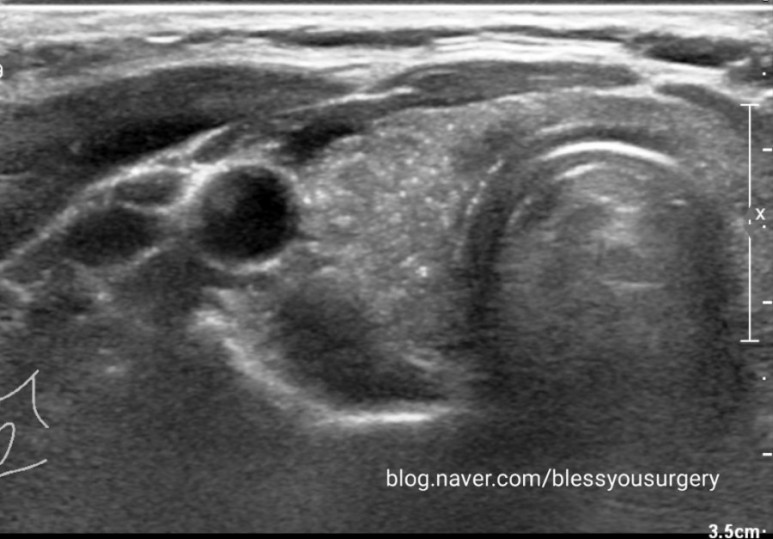

45세 여성의 건강검진상 우연히 발견된 오른쪽 갑상선 미세석회 초음파 사진입니다결절형이 아닌 우측 갑상선 전체에 퍼져 있는 백사립과 같은 미세한 미세석회화에서 세침검사를 실시하여 검사 결과 갑상선 유두상암 진단을 받았습니다.

진단은 초음파를 통하여 갑상선 결절의 크기 및 위치를 확인하고, 세침 검사를 통하여 작은 바늘로 혹에서 세포의 일부를 채취하여 진단합니다.갑상선 유두암의 경우 갑상선 호르몬의 수치는 거의 정상으로, 혈액 내 갑상선 글로불린이라는 물질은 전이된 갑상선 유두암에서 증가합니다.컴퓨터 단층 촬영, 방사성 요오드 스캔, 양전자 단층 촬영 등으로 전이 가부를 평가합니다.